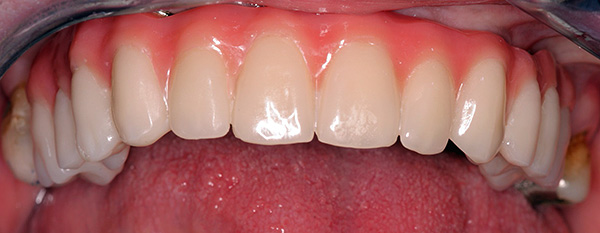

Ecco la protesi sull'impianto:

E sotto la foto mostra farfalla protesica (in realtà, questa è una protesi temporanea, tuttavia, molte persone la usano come permanente):